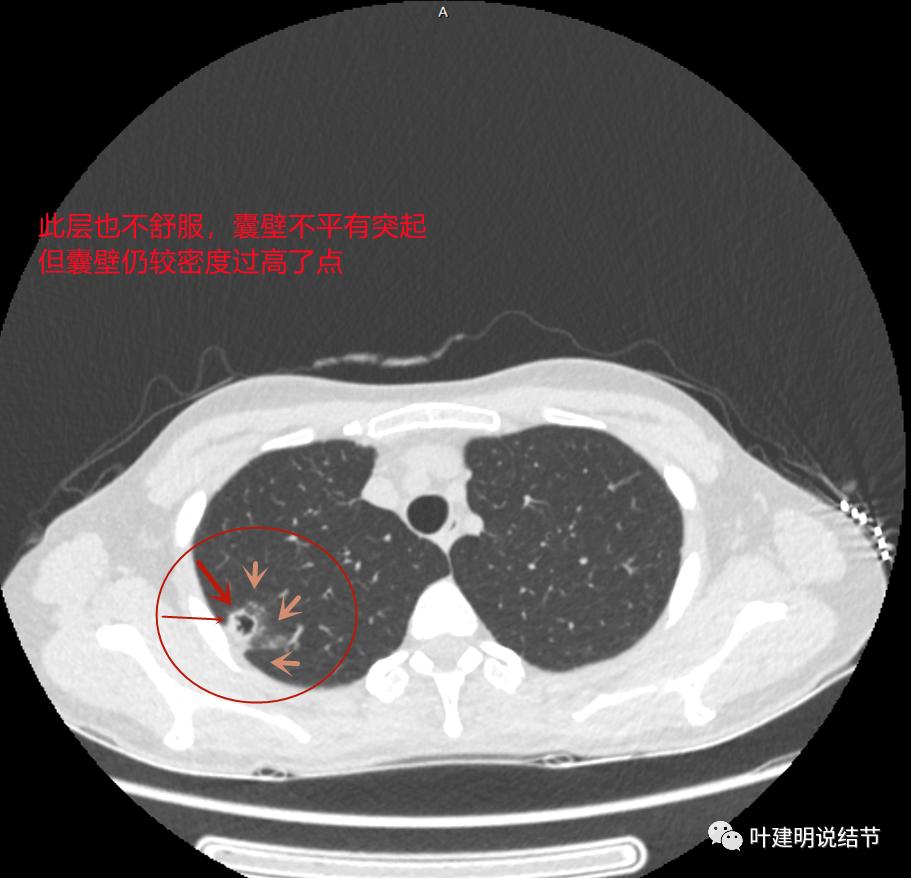

上图与恶性较为符合,空洞性病灶,壁厚薄不均,增厚部分还凹凸不平(细红色箭头所指)

上图磨玻璃部分密度过低,且与正常肺组织界限模糊(砖色箭头),粉色箭头示囊壁密度过高的点状,蓝色箭头示邻近胸膜处的增厚

上图也像恶性,但整个囊壁的密度感觉过高了点,边缘磨玻璃淡、散且模糊,邻近胸膜有增厚